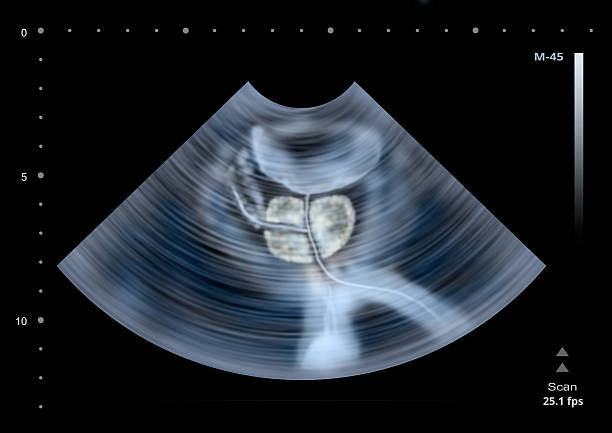

남성 생식기의 요로계와 직접적 연관이 있는 전립선은 사과 모양으로 배꼽 아래쪽에 위치해 있으며 상당히 중요한 역할을 하고 있습니다. 전립선은 사정을 조절하고, 정자의 움직임을 돕는 전립선 분비액을 만들어냅니다. 이 분비액은 정자의 영양 공급과 이동에 필수적인 성분을 포함하고 있습니다. 또한, 전립선은 방광을 둘러싸고 있는 방광 경화근과 골반 바닥 근육에 대한 지지 구조 역할을 할 수 있어 상당히 중요하나 전립선에도 암이 발병될 수 있어 초기에 원활한 대응을 해야만 합니다. 그럼 이번 시간에는 전립선암 초기증상에 대해 자세히 정리해보겠습니다.